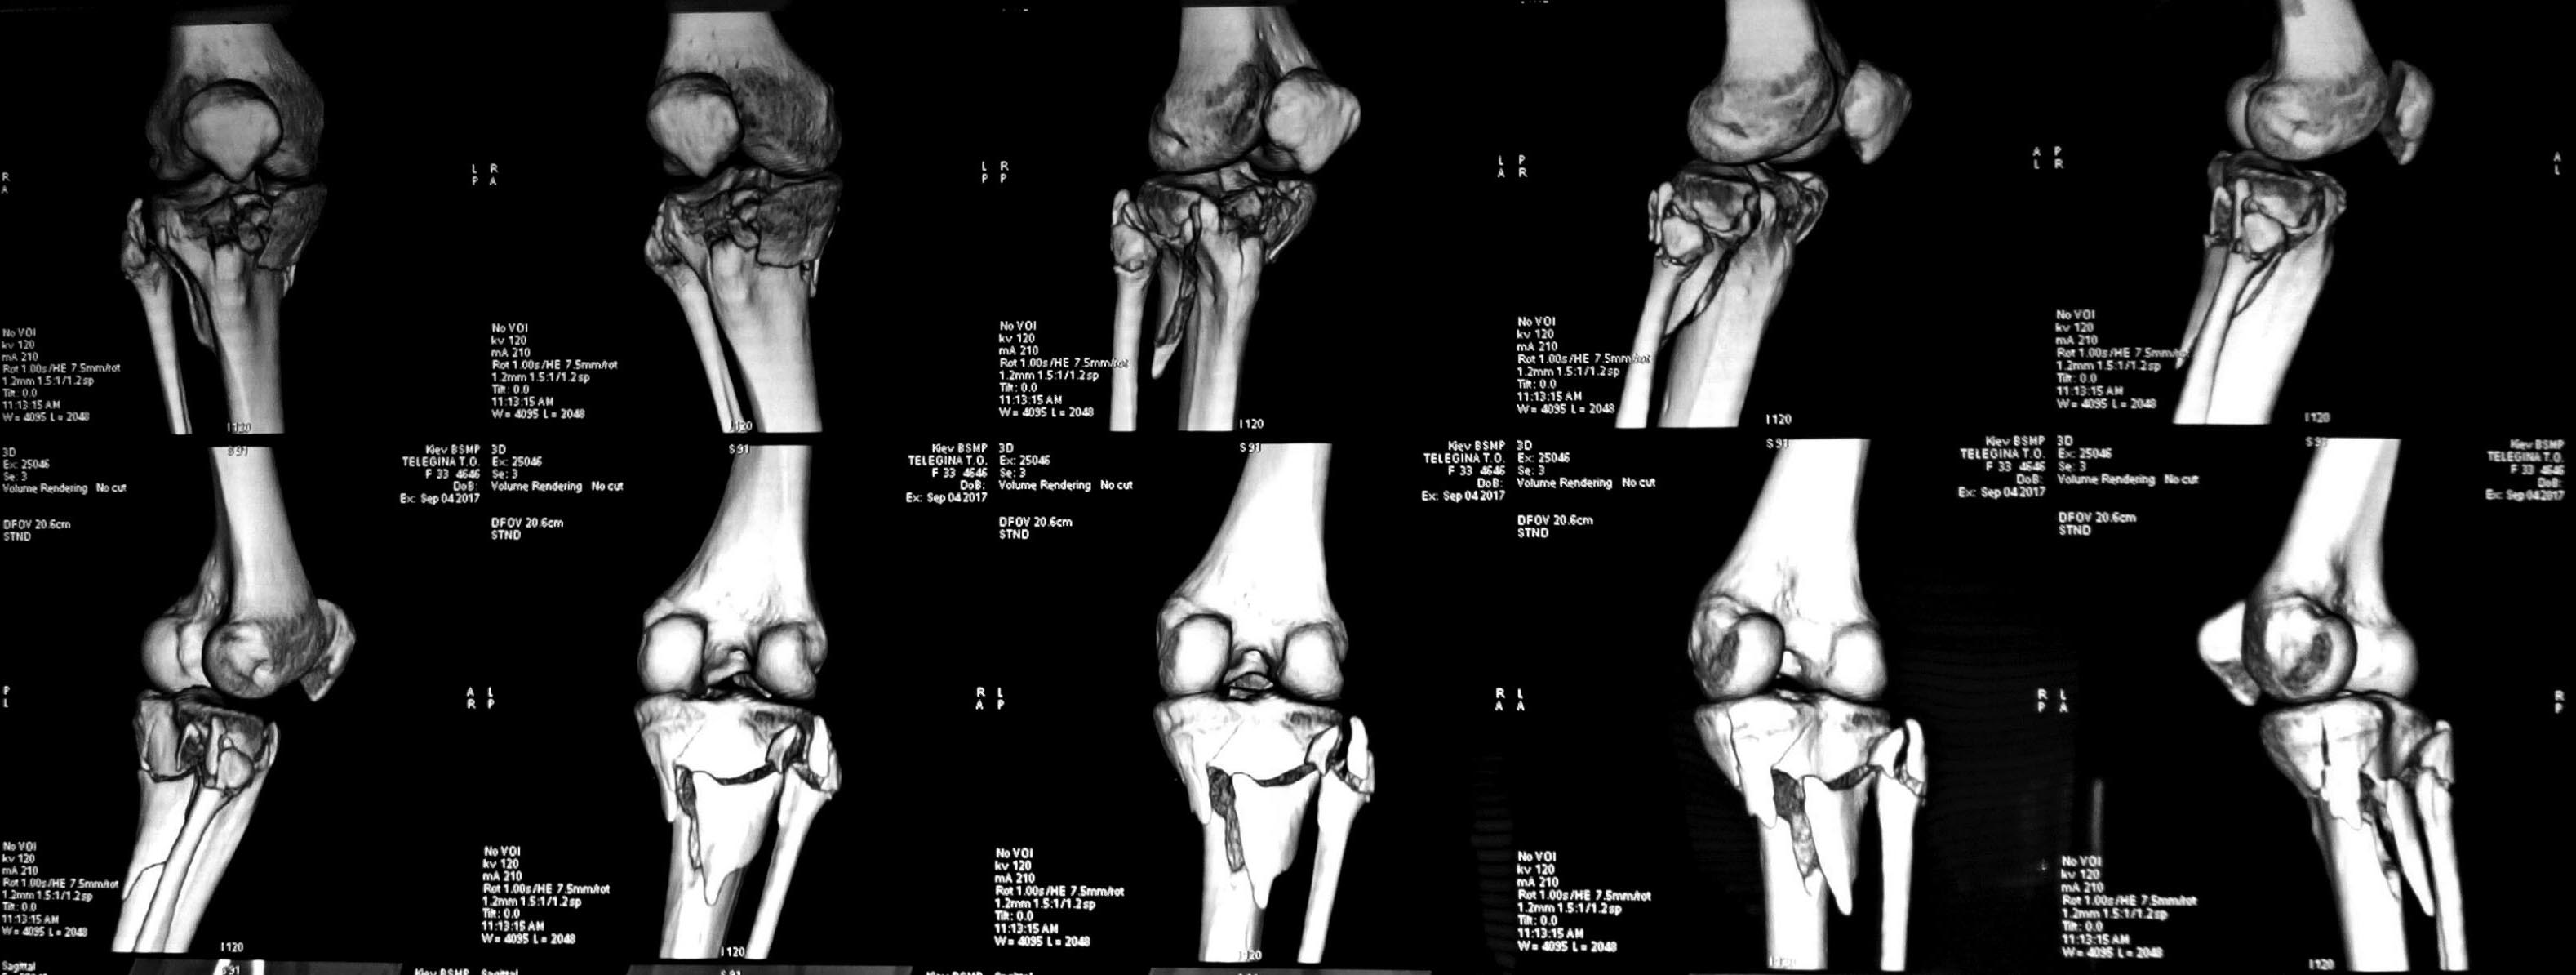

Добрый день дорогие коллеги,прошу совета.Молодая пациентка с переломом ПЭМ голени,фрагментацией fibular head и нейропатией peroneal n.(подобное сочетание у нас не часто).

Мягкие ткани компенсированы, планируется реконструкция из 2-х доступов, однако разделились мнения касательно целесообразности ревизии нерва,репозиции и фиксации перелома fibular head.

3х колонный перелом проксимального плато большеберцовой кости. Не очень понятно, сломан ли заднемедиальный край. Если сломан то 3 доступа-заднемедиальный, медиальный и латеральный. Если нет,то можно обойтись 2мя доступами. Латерально заходить надо не передне-латеральным доступом,а чисто латеральным. Доступ описан в иностранной литературе и некоторых современных переведенных на русский язык изданиях. Данный доступ как раз предназначен для остеосинтеза латерального и заднелатерального фрагмента плато,при нем выделяется как раз и общий малоберцовый нерв и ветвь,идущая через шейку малоберцовой кости,поэтому сразу можно и ревизию сделать. И из этого же доступа потом головку и зафиксировать